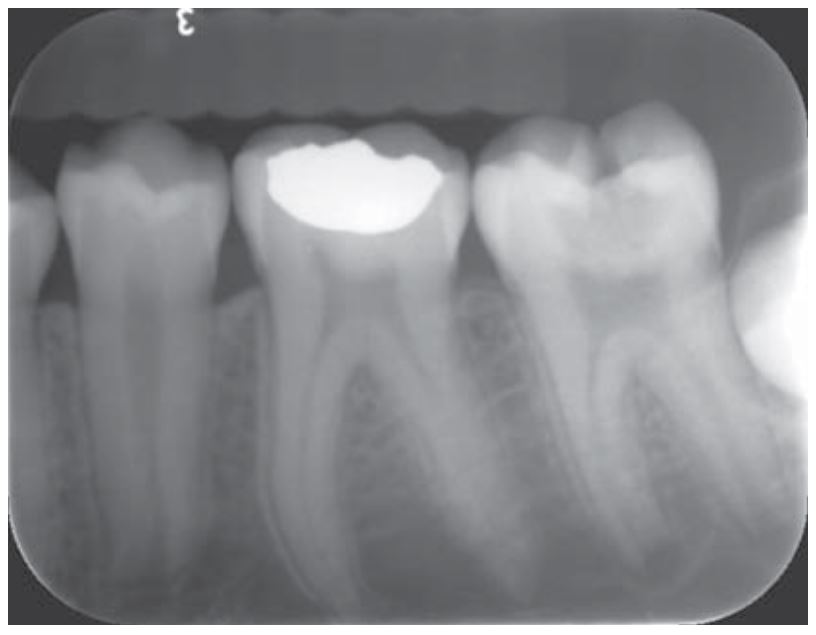

Vật liệu: GI (Vitrebond) và canxi hydroxit (Dycal) (H10.2).

Độ pH cao của canxi hydroxit trong Dycal giúp kháng khuẩn và giúp tái khoáng.

GI có 2 loại là loại lót nền và loại trám kết thúc. Loại GI thường được sử dụng nhất là Vitrebond (3M ESPE). GI trám kết thúc gồm Fuji II, Fuji IX (GC), Ketac Molar (3M ESPE) và Photac Fil (3M ESPE). Nhìn chung GI là một vật liệu trám tốt giúp bảo vệ tủy, ngăn ngừa vi khuẩn và giúp tái khoáng nhờ khả năng phóng thích Fluoride.